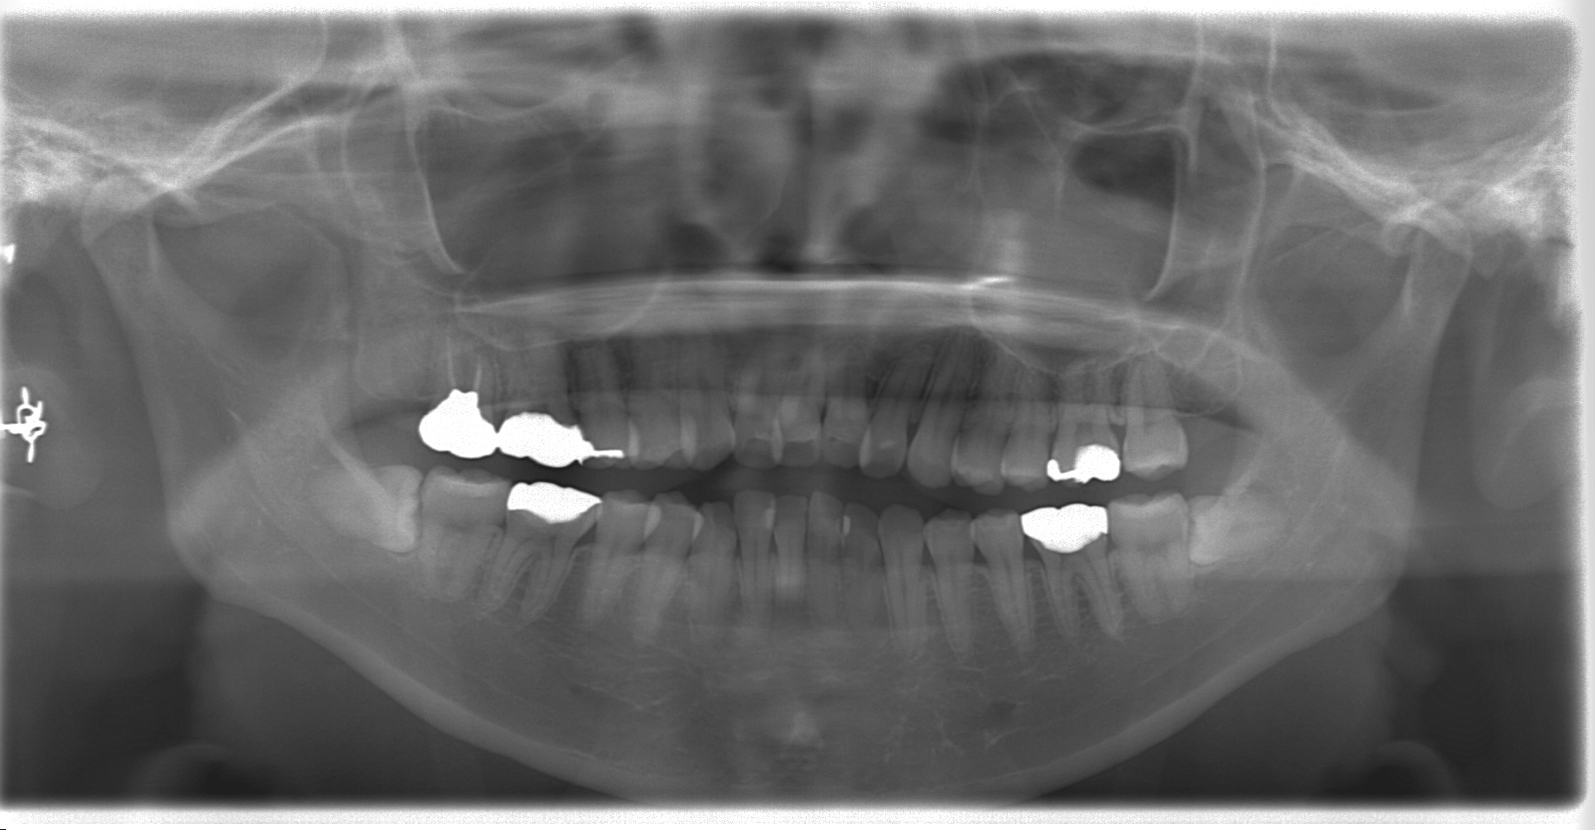

横向きに埋まっている親知らず 下の二本の親知らずは横向きに埋まったままです。 上の二本の親知らずは、斜めになって埋まっています。 レントゲン写真の様に上下4本とも正常に生えてこない親知らずは決して珍しい事ではありません。 この様に埋没した親知らずは、矯正治療をする、しないにかかわらず、 抜歯をする ことをお薦めします。 なぜなら、歯磨き歯科治療横向きに埋まっている下の親知らずの抜歯 千種区池下の優しい歯医者さん 阿部歯科 院長阿部丈洋です。 今回は皆さんが「気になっているけれど、なかなか怖くて聞けない・・・」という 下の親知らずの抜歯の内容とその手順 について、詳しくご説明をしたいと思います。親知らず症例 半分埋まっている親知らずを抜きたい。 。年齢・性別 30代・女性 来院動機 下の左右の親知らずが少し生えていて、疲れると腫れたり痛んだりするので抜きたい。 治療内容 Before 抜歯前のレントゲン写真 下の左右に親知らずが埋まっています。

親知らずの抜歯 骨に埋まった親知らず についてvol2 先週、抜歯した患者さんの抜歯する前のレントゲン写真です。 完全に骨に埋まって神経に近接、骨と一部癒着、なかなか手強い親知らずでしたが 30分で痛みを感じさせずにいつも通りに抜けました。 一週間後の経過も非常に良くて安心しました! 時折疼く完全に埋まっている親知らずを抜歯するかどうか こんにちは、いつもお世話になっております。 私は下の左右に 親知らず があります。 完全に横向きで 歯茎 に埋まっています。 酷く痛む事はありませんが、 発熱 した後や酷く疲れた時にうずくような感覚になる事がありました。 現在、胃腸 風邪 で39度近くまで発熱した後、両方にまたうずきが 親知らずは1度痛んだら抜いたほうが良いというのをこのサイトを見て知ったので、この 親知らずを抜歯 しようと考えています。 そこで心配なのが、歯科医の先生に 抜歯 するなら歯茎を切開しなければならないと言われました。 完全に埋まっている親知らずを切開するのはわかりますが、この程度(半分~1/3)埋まっている場合でも切開しなければなら